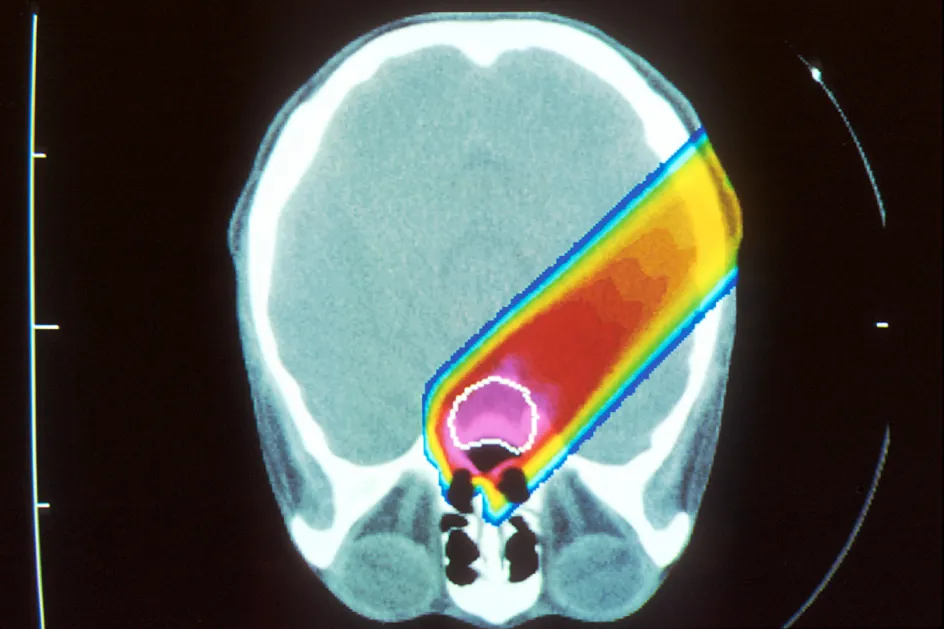

Other types of radiation are more specialized. Stereotactic radiosurgery delivers high radiation doses with a great degree of precision. Proton therapy uses protons to deliver radiation doses to the tumor (Figure 31.17). Intensity-modulated radiation therapy uses computer-controlled beams of radiation from multiple angles.

X-ray image showing tumor in red with proton beam in yellow

Figure 31.17 The tumor is noted in red with a proton beam noted by the yellow line. (credit: “Proton Beam Therapy” by NIH/National Cancer Institute, Public Domain)